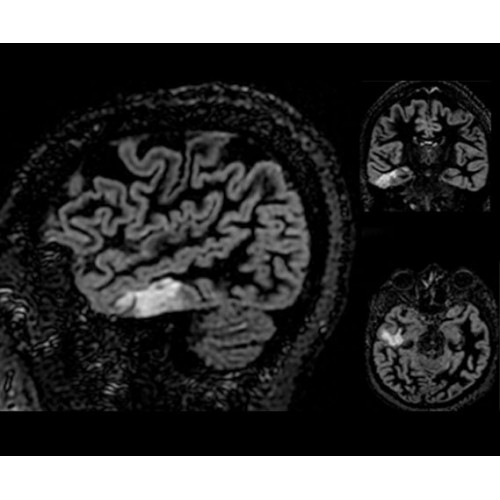

В систему SIGNA PET/MR встроены запатентованные детекторы кремниевого фотоумножителя (SiPM) и сверхчувствительные кристаллические сцинтилляторы на основе лютеция толщиной 25 мм. Благодаря этому обеспечивается исключительная чувствительность и возможность использования времяпролетной диагностики (TOF).

Кроме того, в результате использования технологии TOF и инновационной технологии реконструкции Q.Clear вы сможете добиться прекрасного соотношения сигнал/шум. А благодаря технологии нулевого времени эхо (ZTE) визуализировать костную структуру без ионизирующего излучения. Все эти разработки для улучшения качества сканирования и точности анализа помогут вам использовать весь потенциал ПЭТ/МРТ.

• TurboTOF — инновационная технология позволяет корректировать коэффициент затухания сигнала и минимизировать потери анатомических данных, создавая МР-систему для количественной визуализации.